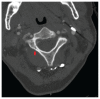

Traumatismes craniocérébraux et médullaires chez une piétonne heurtée par une trottinette électrique